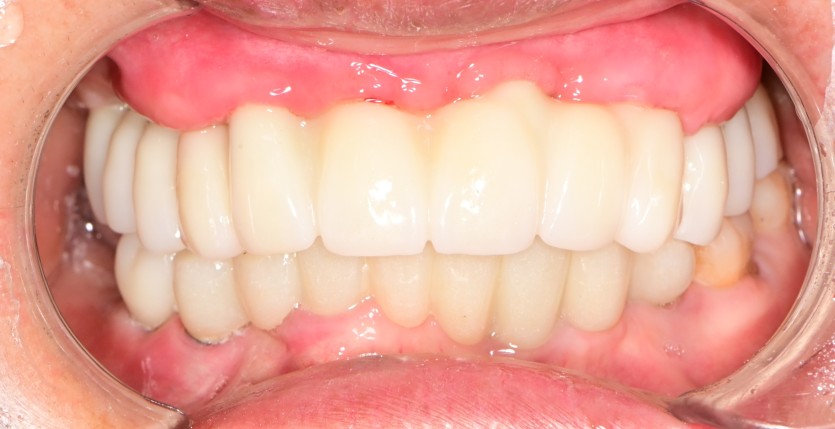

상악 전체 임플란트 증례입니다.(하악 일부)

11개의 임플란트로 완성하였습니다.